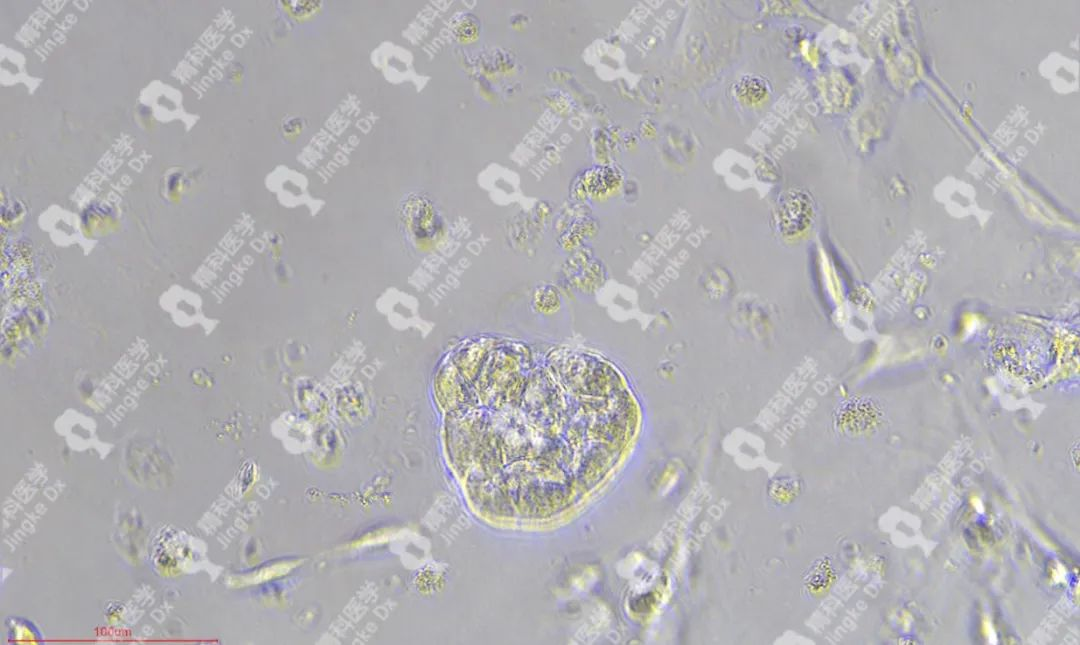

精科類器官培養(yǎng)相關(guān)服務(wù) 精科醫(yī)學(xué)作為類器官技術(shù)轉(zhuǎn)化先行者致力于推動類器官技術(shù)的轉(zhuǎn)化與應(yīng)用,對基于類器官培養(yǎng)擁有成熟的技術(shù)與經(jīng)驗。精科類器官團(tuán)隊技術(shù)深耕十余年,擁有國內(nèi)頂級的類器官團(tuán)隊,超微量建模技術(shù)成功率高達(dá)95%以上,有成功建模30+種腫瘤的經(jīng)驗(包括上述子宮內(nèi)膜癌、宮頸癌和卵巢癌)??梢蕴峁┌惼鞴俳Ec保存(建模、凍存、傳代)、類器官檢測(類器官H&E染色、免疫組化、藥物敏感度篩選)等多種類器官相關(guān)服務(wù)。檢測服務(wù)最快可在十個工作日內(nèi)完成,更好為患者爭取治療時間。 ★ PIC.01 精科卵巢癌類器官圖像 ★ PIC.02 精科宮頸癌類器官圖像 ★ PIC.03 精科子宮內(nèi)膜癌類器官圖像